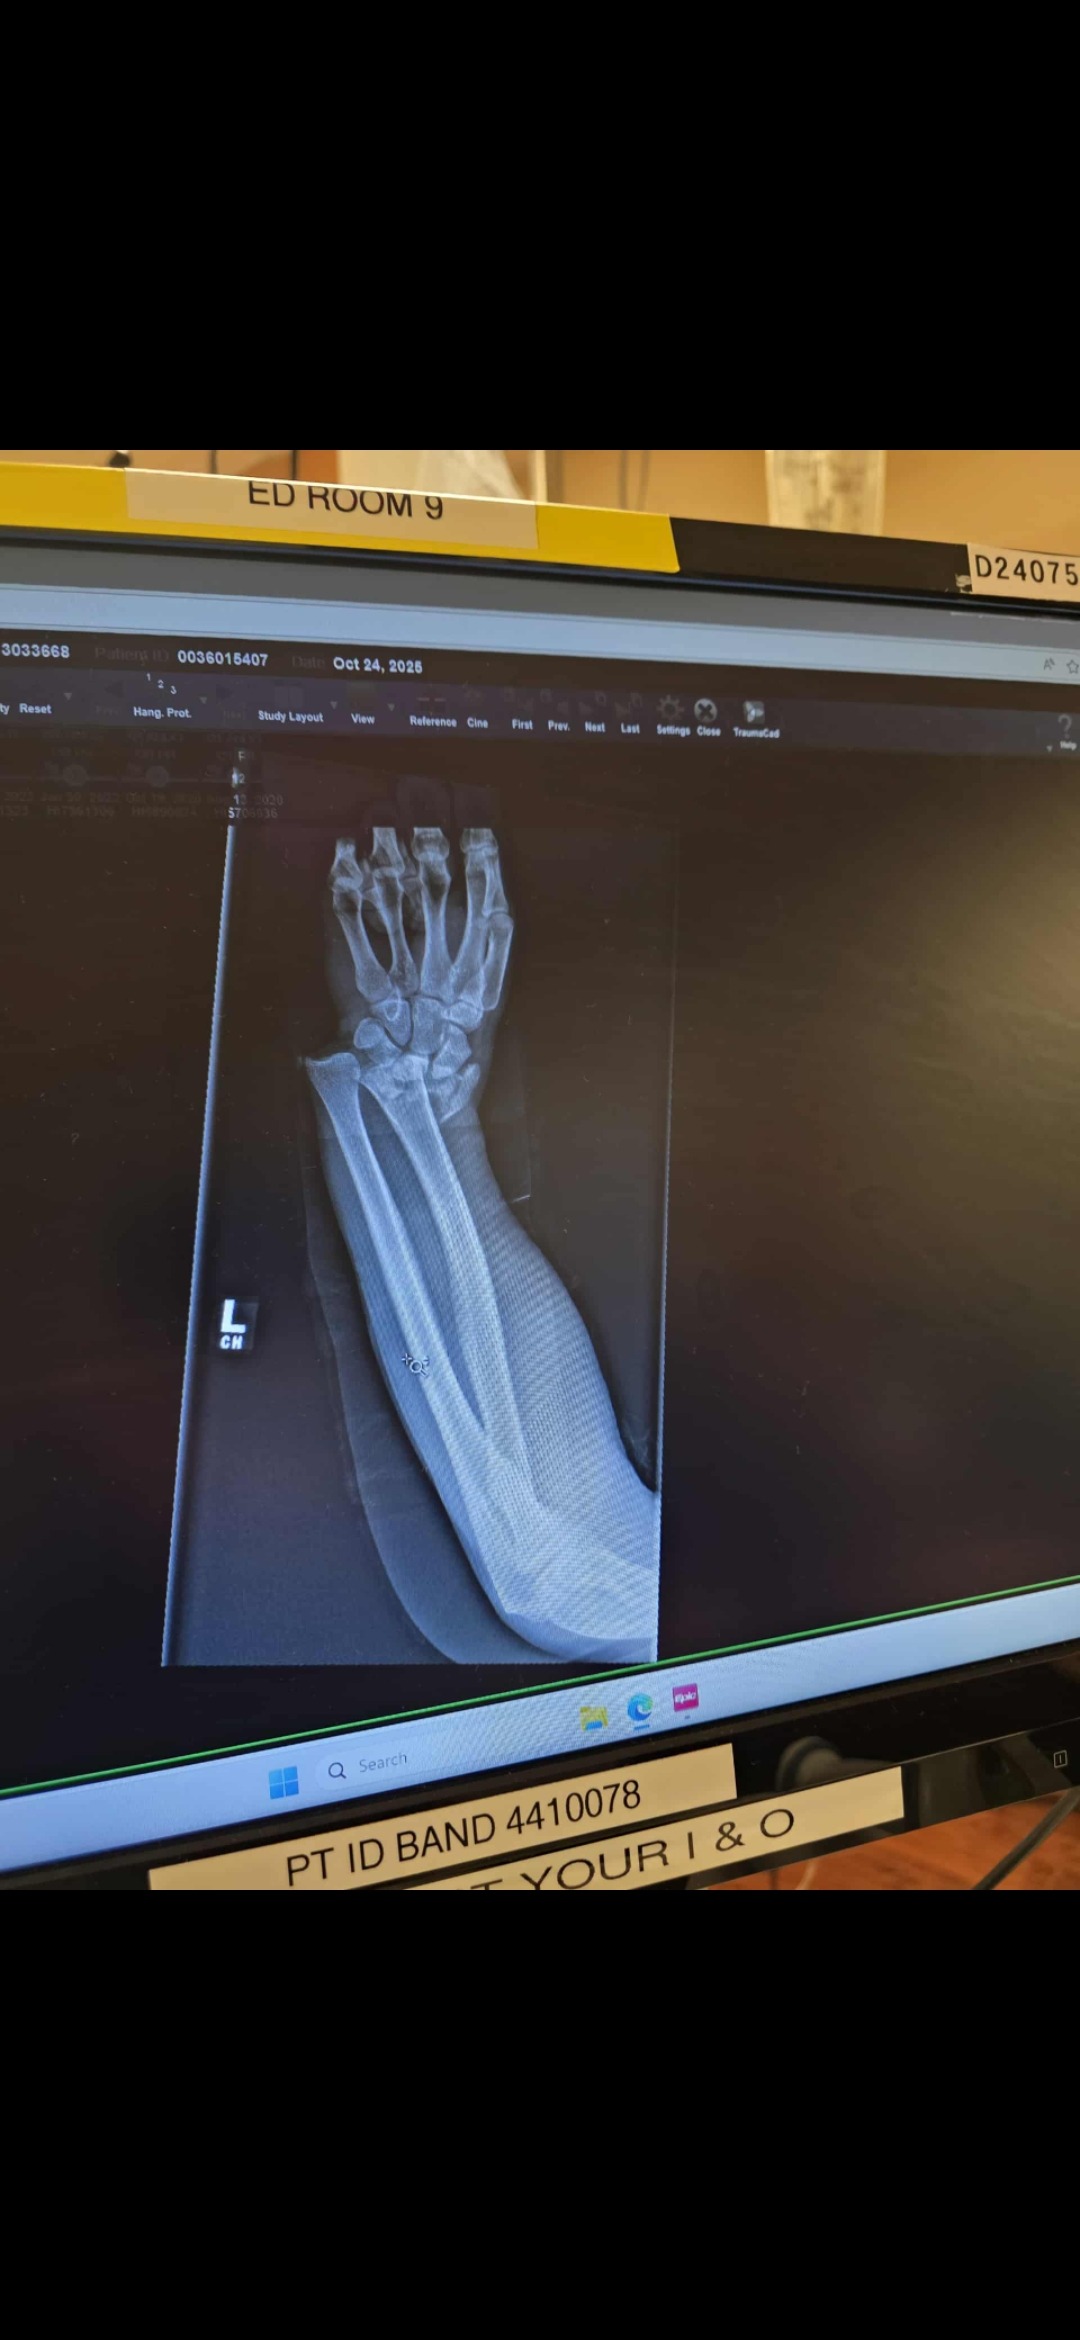

Tanner suffered a serious injury to his left wrist. Pictures of the injury are pretty graphic and are included with this to show the severity of his injury. In simple terms he severely dislocated and broke his wrist to the point that the specialist does not know if hardware can repair it.

Tanner has had four procedures in three days (Oct. 24th-27th) with numerous surgeries in the near future. Right now, they are trying to stabilize his wrist to avoid a fusion, but the prognosis is not looking good. At this point Tanner is looking at a debilitating injury that will more than likely render that arm disabled. All future surgeries will be aimed to stabilize and seek comfort for him.